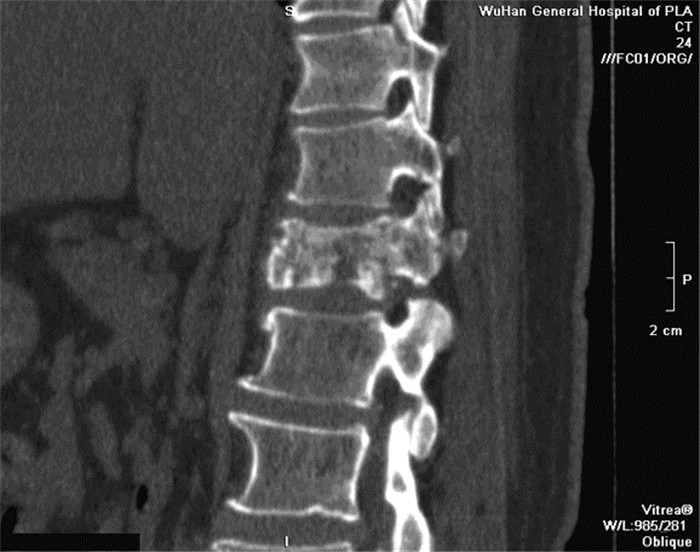

REN Yong, QI Manli, FENG Junming, CHEN Shousong. Thoracic Vertebrae Metastasis as First Symptom of Clear Cell Carcinoma of Thyroid Gland: A Case Report[J]. Cancer Research on Prevention and Treatment, 2017, 44(4): 311-312. DOI: 10.3971/j.issn.1000-8578.2017.04.016

Thoracic Vertebrae Metastasis as First Symptom of Clear Cell Carcinoma of Thyroid Gland: A Case Report